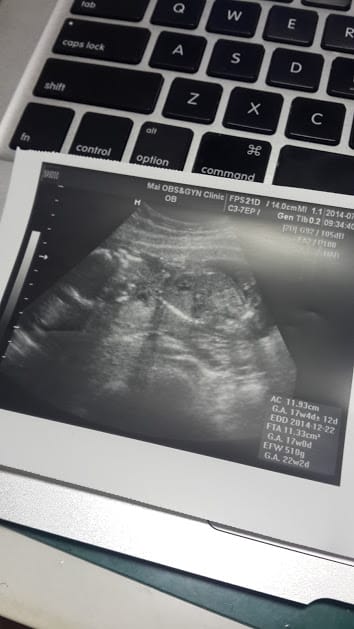

終於捱到第二次產檢了! 肚子大到視覺感已…